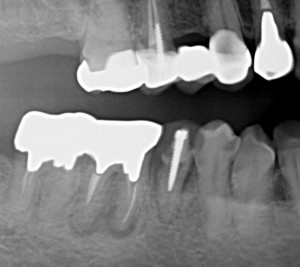

術前の46番を見て頂くと、根尖病巣があるのはわかりますが近心根は2根で、どっちかが途中までしか形成できなかったのかな~くらいのイメージで治療を開始。

長すぎてパントモ上では普通のGPと誤認していました。

デンタルって大事ですね。